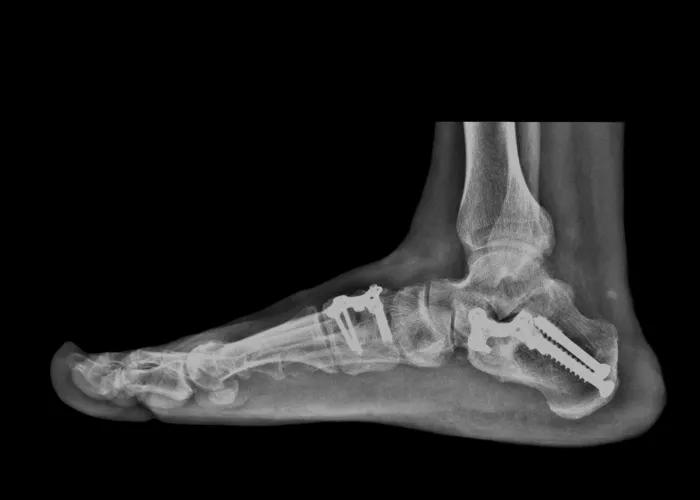

Bones that are dislocated or broken

However, if there is pain or mobility issues present, treatments may include bracing, prescribing NSAIDs for pain and inflammation, and even surgery in some cases of torn tendons or broken bones.